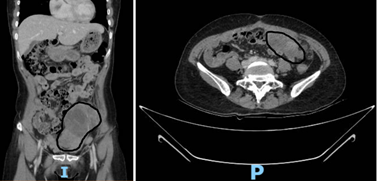

Sau khi có chẩn đoán xác định, bệnh nhân được chỉ định hóa trị 6 chu kỳ. Nhờ đáp ứng tốt, khối u thu nhỏ đáng kể. Đến lần phẫu thuật thứ hai (second look surgery), ekip ghi nhận: nhiều khối u thành bụng, u vùng chậu và u mạc treo đại tràng (T) kích thước từ 4–10cm, cùng khối u buồng trứng (P) 5cm. Các khối u chắc, giới hạn rõ, có thể cắt bỏ được. Các bác sĩ đã tiến hành cắt bỏ khối u và các tổn thương liên quan, đạt được tiêu chuẩn triệt để về ung thư học.

Hình 2. Hình ảnh vị trí to nhất của khối u trên CTscan bụng theo các mặt cắt đứng dọc và ngang sau khi hóa trị